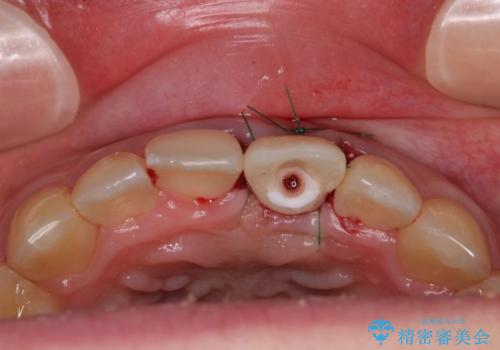

歯根吸収した前歯 短期間でのインプラント治療

小学生の時に前歯を殴打したとのことで、歯根が吸収してしまい、抜歯が必要と判断されました。

抜歯、インプラント埋入、仮歯の装着が同時に可能な1DAYインプラントを行いたいところでしたが、吸収による歯肉の炎症が著しいため、抜歯後に炎症が治まるまで待機し、極力早期にインプラント埋入を行うこととしました。

長い間歯肉が炎症を患っていたため、炎症改善後には歯肉がやや退縮した状態となっていました。